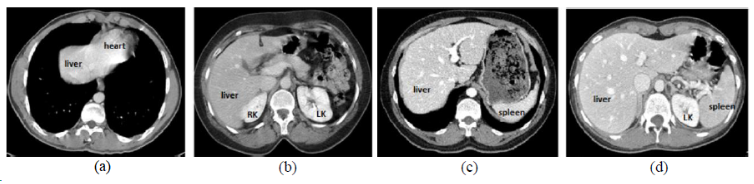

| CHAOS | 肝/肾/脾 | 分割 | CT+MRI | 40CT+120MRI | 0/1标签 | dcm | CC 4.0 |

CHAOS是一个多脏器,多模态分割数据集。